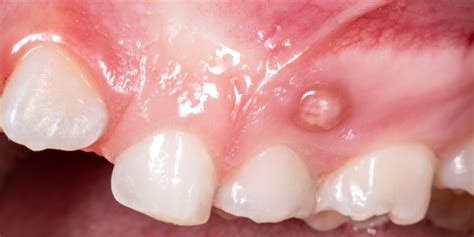

Cuando se forma la fístula dental, aún no causa dolor. Al principio, la zona afectada se hincha. Las encías se enrojecen y hay una sensación de tensión en el diente. A continuación, se forma una ampolla en la encía, encima o debajo del diente afectado, que se llena de pus a medida que avanza. La fístula dental empieza a palpitar y doler. Puede que incluso se te hinche la cara del lado afectado y te duela la cabeza. Esto puede tardar varias semanas en desarrollarse.

- Absceso dental: La presencia de una fístula dental puede dar lugar a la formación de abscesos dentales. Un absceso dental es una acumulación de pus causada por una infección bacteriana en el tejido dental. En el caso de una fístula dental, el absceso puede manifestarse como una protuberancia roja y dolorosa en las encías cerca del diente afectado. Esta protuberancia puede estar acompañada de sensibilidad al tacto y al calor, así como de hinchazón en el área circundante.